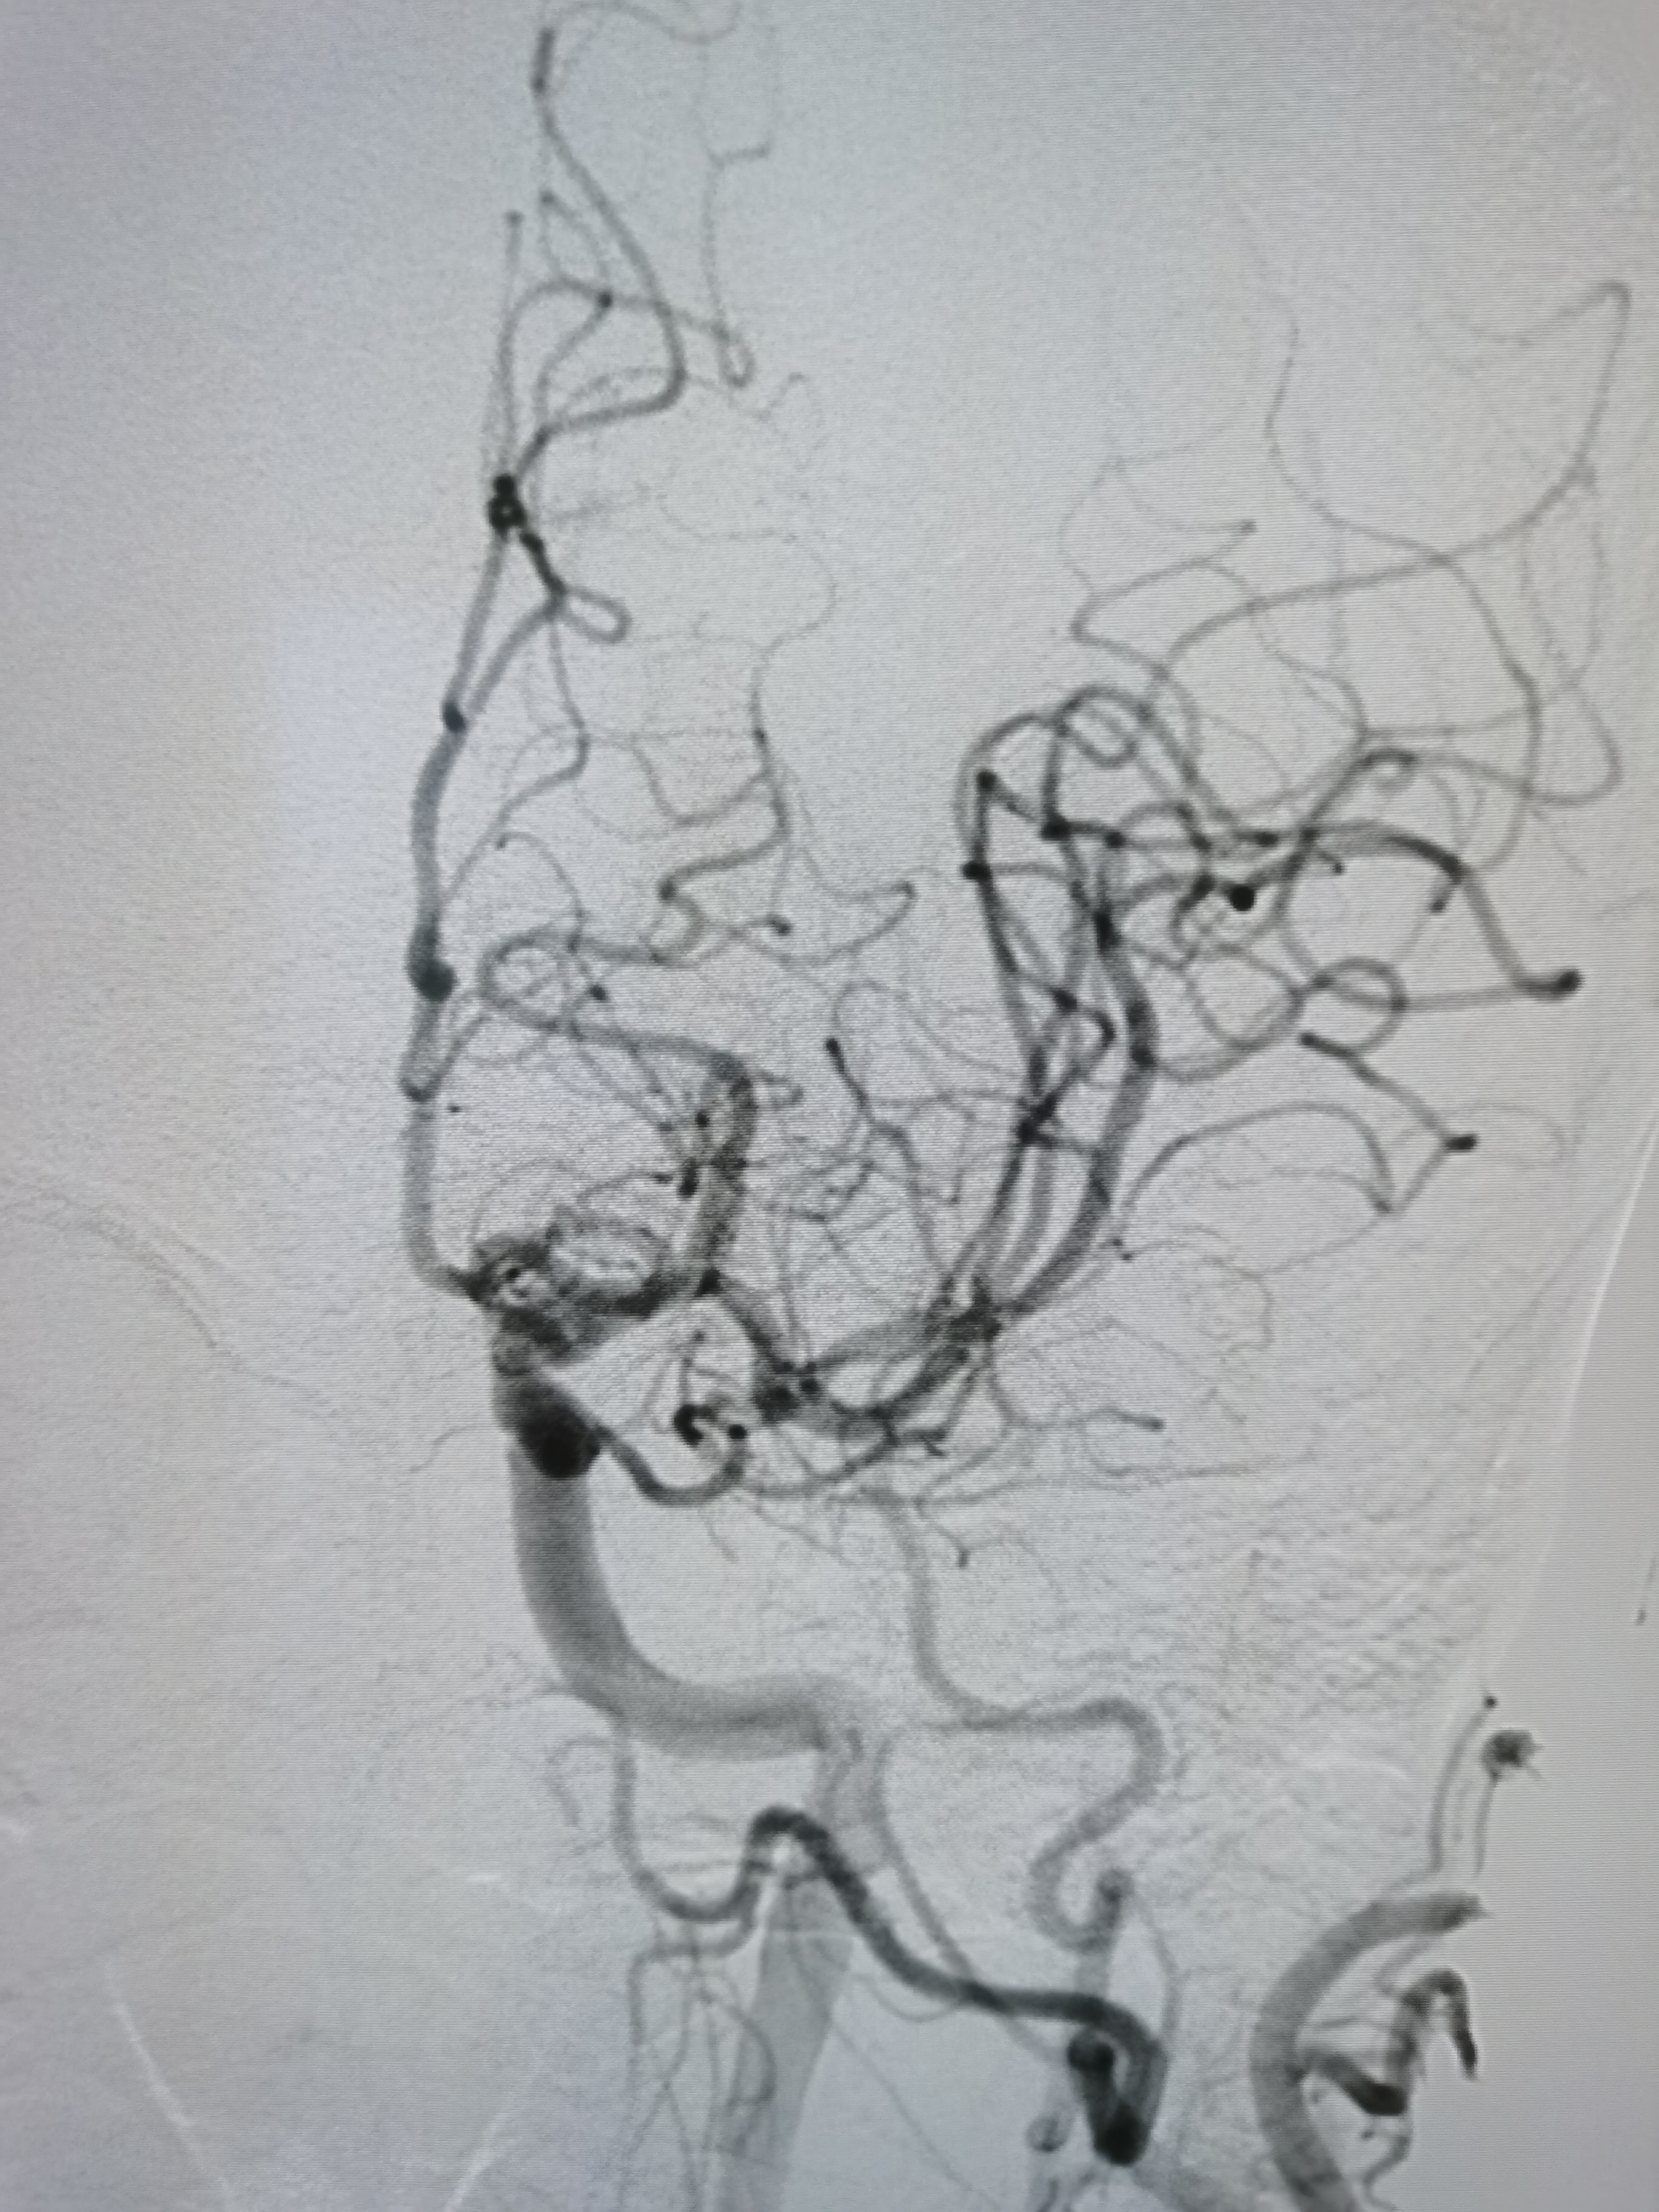

右侧胚胎型大脑后动脉。

颅内段显影良好。

左侧胚胎型大脑后动脉,颅内血流明显改善。